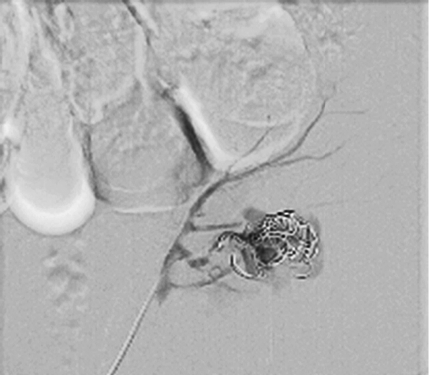

Right femoral artery was punctuated under local anesthetic. Inferior segmental artery was selectively cathe­terized and pseudoaneurysm was visualized. A microcatheter was inserted into segmental branch (Figure 4).

Figure 4. Renal pseudoaneurysm catheterized and visualized using contrast solution